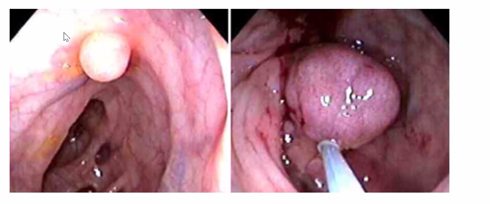

what is seen on this colonoscopy

Small polyp

Diverticulae in the bag

Tubular adenoma – benign polyp. Glands form test tube shape structures histopathologically.